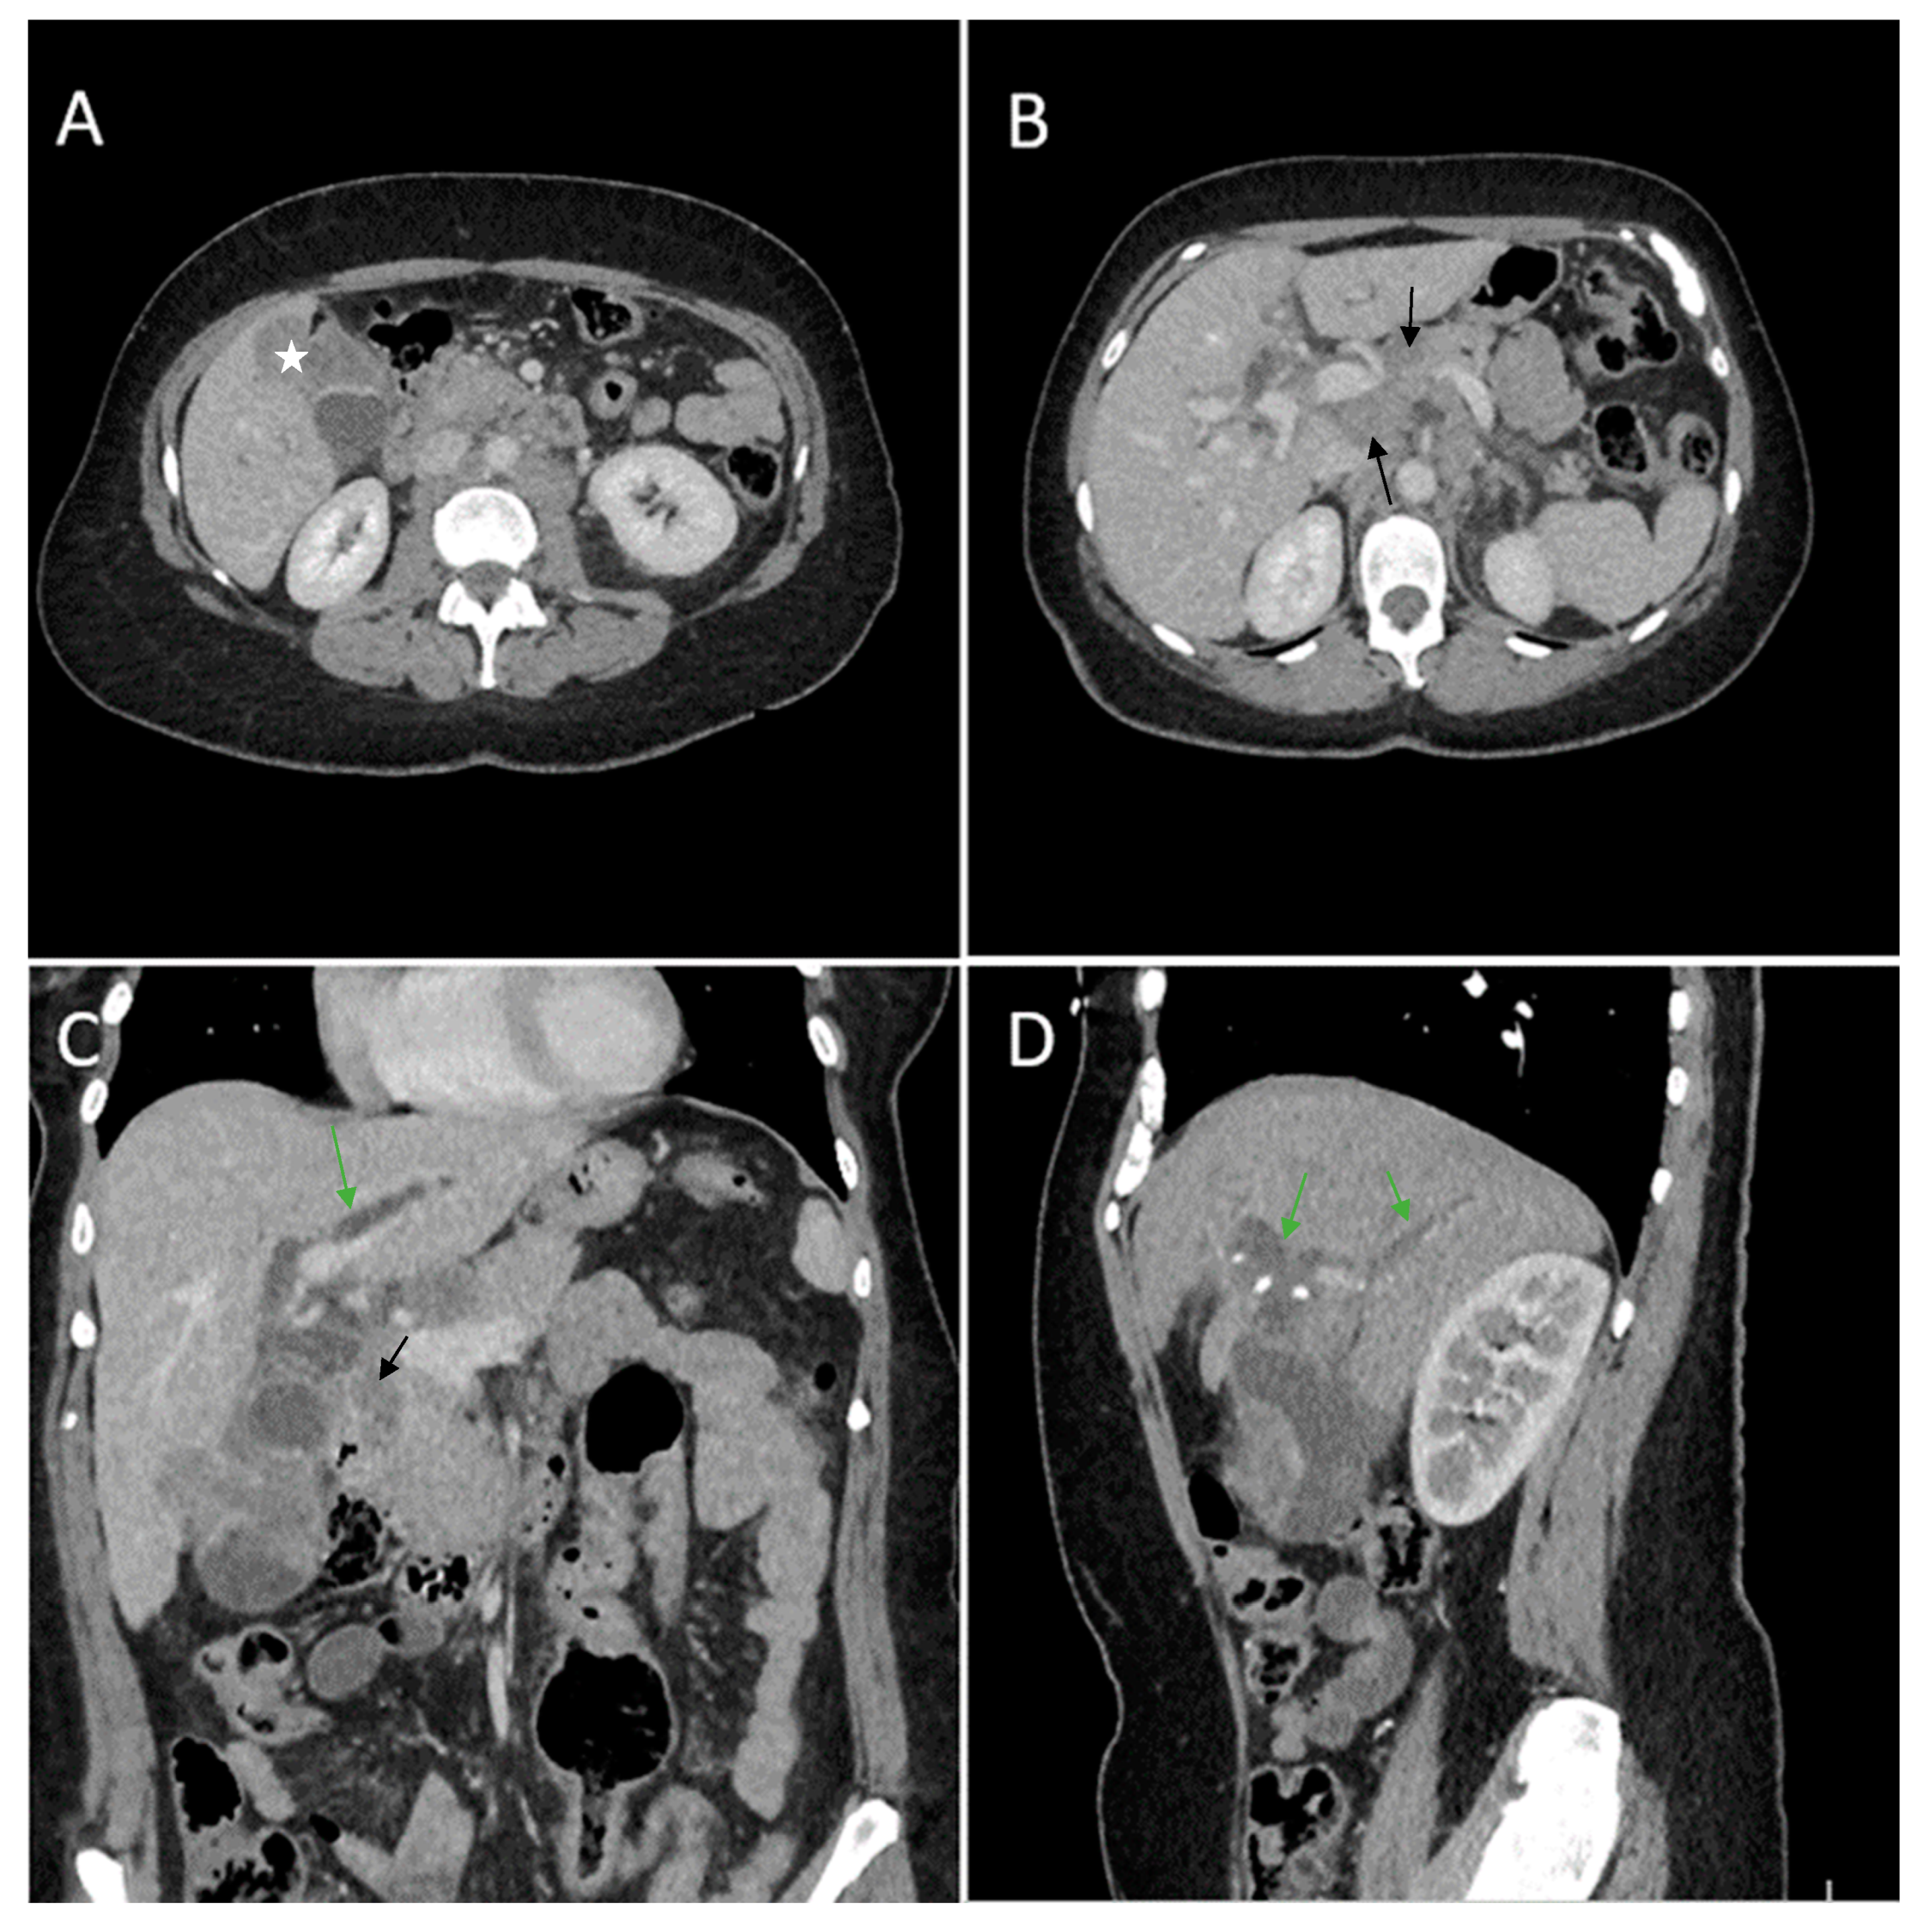

Figure 4. Multiplanar sections of contrast-enhanced CT acquisitions richly illustrating gallbladder carcinoma. (A) Heterogeneous ill-defined intraluminal irregular mass located predominantly in the gallbladder fundus (white star). (B) Multiple lymphadenopathies with areas of necrosis included (black arrows). (C) Gallbladder mass presents extension in the surrounding liver (segment V). (D) Intrahepatic biliary dilatation in both hepatic lobes, predominantly perihilar (green arrows).

Contrast-enhanced emergency CT was performed (Figure 4), which richly highlighted a large heterogeneous intraluminal gallbladder mass, localized in the gallbladder fundus, measuring 58/34 mm, irregular, peripheral contrast enhancement on arterial and venous phase and with central hypodensity suggestive of areas of necrosis, extending to the surrounding liver (segment V) (Panel A and Panel C). CT showed a gallstone (17 mm) wedged in the gallbladder neck and intrahepatic biliary dilatation (Panel C and D). The common bile duct was dilated due to the presence of a possible tumoral extension to biliary tract or by the compressive effect of the multiple hilar lymphadenopathies; mesenteric, celiac and retroperitoneal lymphadenopathies with areas of necrosis, measuring up to 25/15 mm were also noted (Panel B). Abdominal contrast-enhanced MRI was performed (Figure 5).